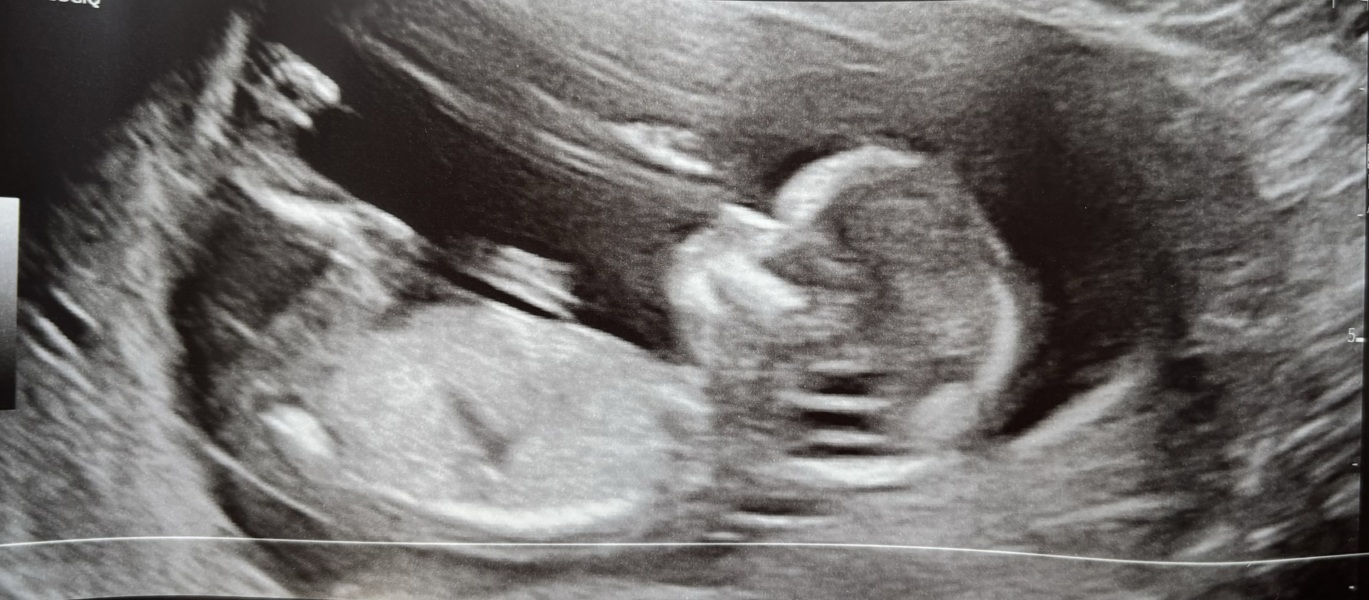

SELE97 · 16/04/2024 16:41

This scan was done last week at 10+6, my mother pointed out that you can see baby's eyes, nose and mouth but I really didn't see this before just looked like a blob to me but now I cant I see a little face. What do people think?

I have my 12 week scan tomorrow so hopefully everything goes okay and a decent photo would be a bonus❤️

@SELE97 I can definitely see eyes, nose, mouth and legs! Good luck for tomorrow!